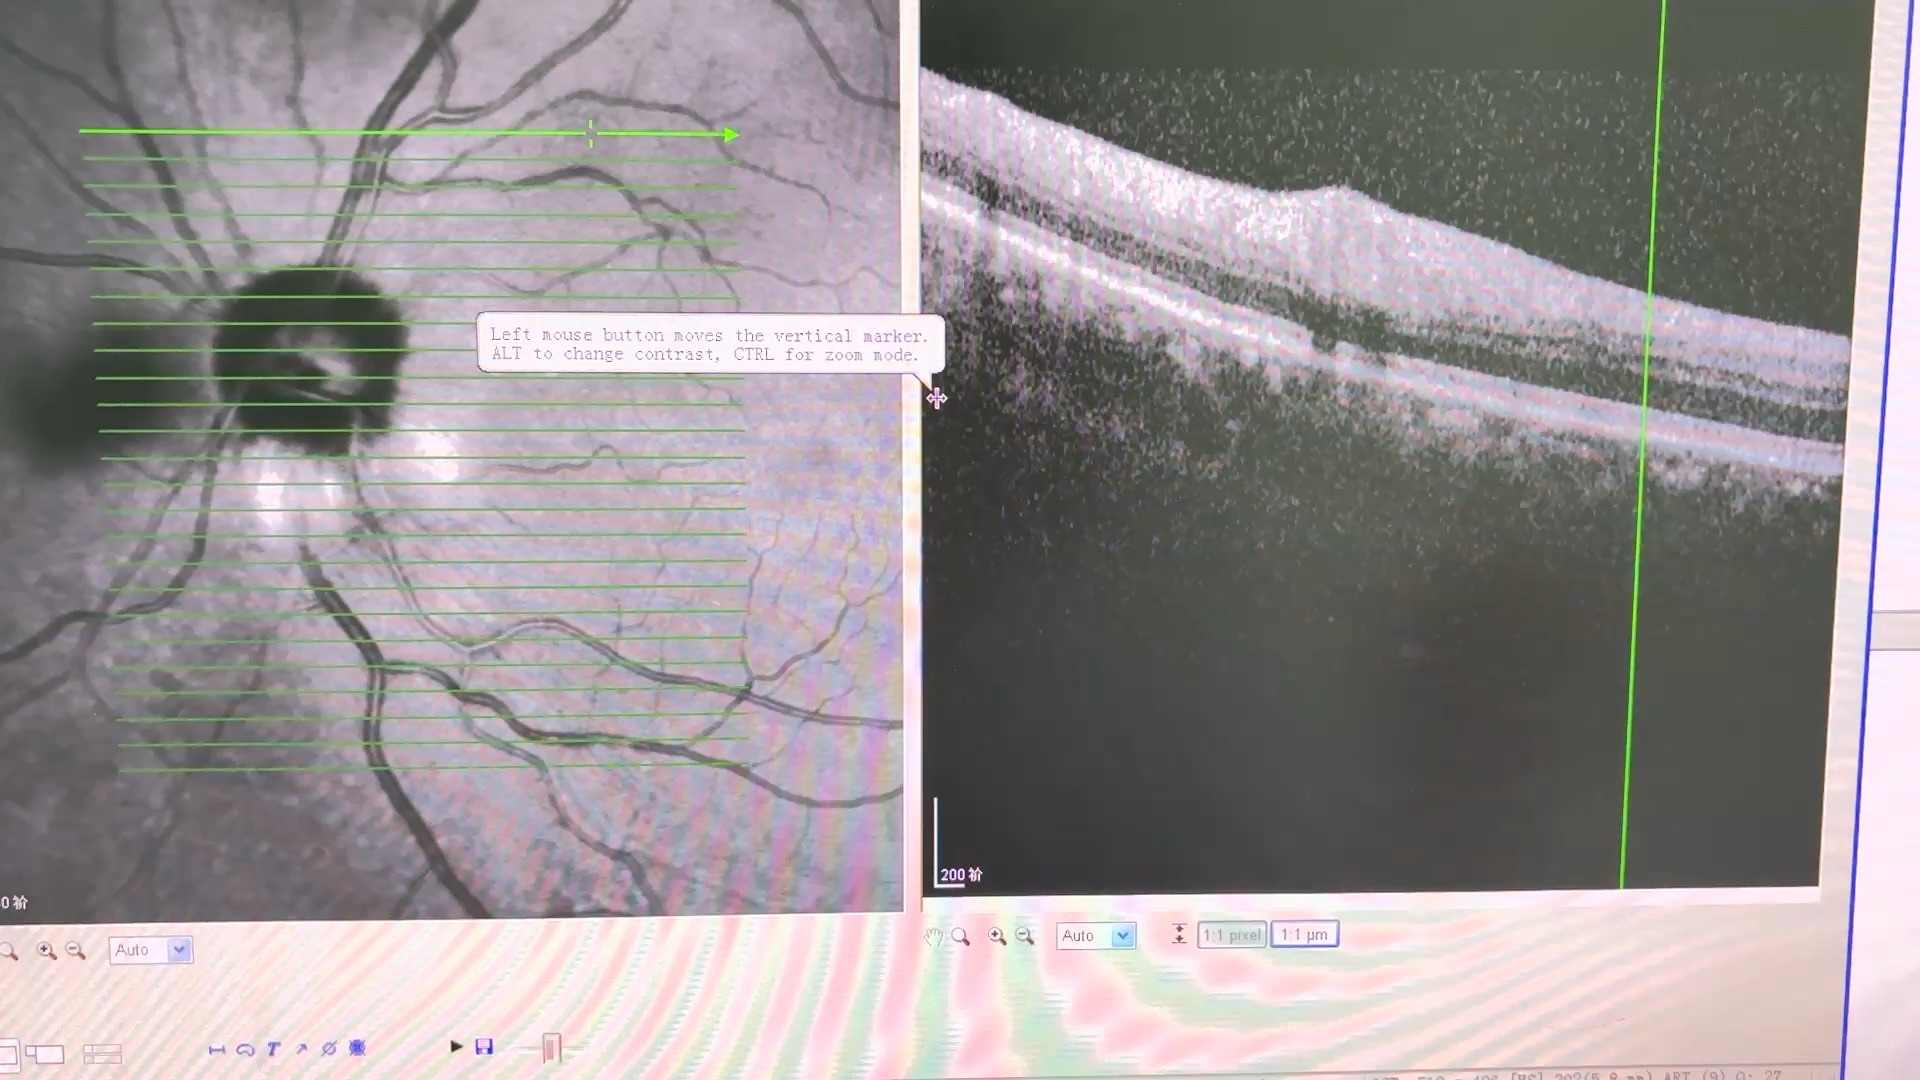

61岁糖尿病患者眼底筛查,视力双眼0.8,晶体皮质轻混浊,眼底见右眼上方,左眼下方圆形病灶。

视盘旁长ODD吗?